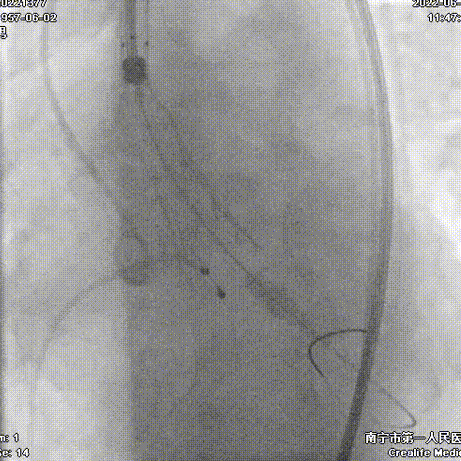

手术过程:

导丝跨瓣

20mm球囊预扩

Snare协助输送器跨瓣

AV26瓣膜定位

AV26瓣膜释放到工作位

AV26瓣膜释放

22mm球囊后扩

术后主动脉根部造影,形态改善

本例手术为重度钙化二叶式病变重度主动脉瓣狭窄TAVR手术,团块状钙化挤压存在移位瓣周漏风险,术前手术团队对患者进行了全面细致的评估,确定假体瓣膜锚定区域范围,制定术前释放策略。球囊第一次通过困难,刘主任当机立断,采用外周小球囊预扩策略,再上20mm主动脉球囊充分预扩。通过球扩预判,果断采取snare辅助输送器顺利跨瓣。

刘杰主任团队通力配合、精准释放,充分利用TaurusElite可回收功能,在瓣膜释放至2/3时,多角度评估瓣膜植入深度、锚定力以及冠脉灌注情况,确认瓣膜植入深度合适、锚定力稳定,缓慢逐个脱钩,进行瓣膜释放。释放后造影显示钙化挤压严重,瓣膜膨胀不良,故选择球囊后扩,后扩后造影显示瓣膜膨胀良好,行血流动力学评估,跨瓣压差从术前220mmHg降至5mmHg,无明显瓣周漏,手术圆满完成。术后10小时拔管,第二天正常下床活动,术后5天出院。